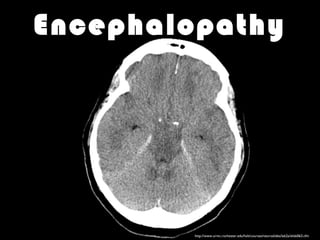

Encephalopathy

http://www.urmc.rochester.edu/hslt/courses/neuroslides/lab2a/slide063.cfm

• #18 Encephalopathy develop very rapidly. Intracranial hypertension (ICH) is a common cause of death. Much of the intensive care management of patients with ALF is aimed at preventing or treating ICH Ventilate to a low normal ETCO2 Try to avoid high PEEP as it can increase ICP and cause hepatic venous congestion Keep well sedated Assess neurology hourly Take standard measures to prevent intracranial hypertension Essentially - treat like a TBI, including use of therapeutic hypothermia, bearing in mind that this may worsen coagulopathy. Some centers routinely use therapeutic hypothermia in acute liver failure, and an RCT is underway

• #19 Lactulose is not routinely indicated While useful in early encephalopathy, there is no good evidence to support its use in high grade encephalopathy and it may interfere with fluid balance and make transplant technically more difficult Seizures should be treated promptly with a benzodiazepine and phenytoin There is no role for prophylactic phenytoin Signs of increased ICP such as anisicoria or drop in GCS should be treated with osmotherapy +/- therapeutic hypothermia